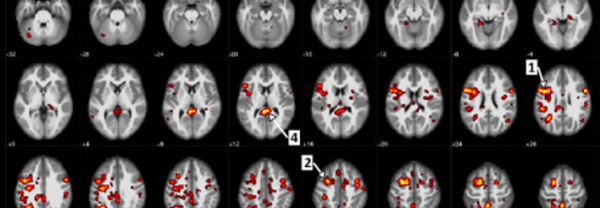

IBM et l’Université de l’Alberta publient de nouvelles données sur des algorithmes d’apprentissage automatique afin d’aider à prédire la schizophrénie

Une recherche innovante en «psychiatrie informatique» utilise l’intelligence artificielle (IA) pour explorer la prédiction et l’évaluation de la maladie. Des scientifiques d’IBM (NYSE : IBM) et l’Université de l’Alberta à Edmonton, Canada, ont publié de nouvelles données dans Nature’s partner...